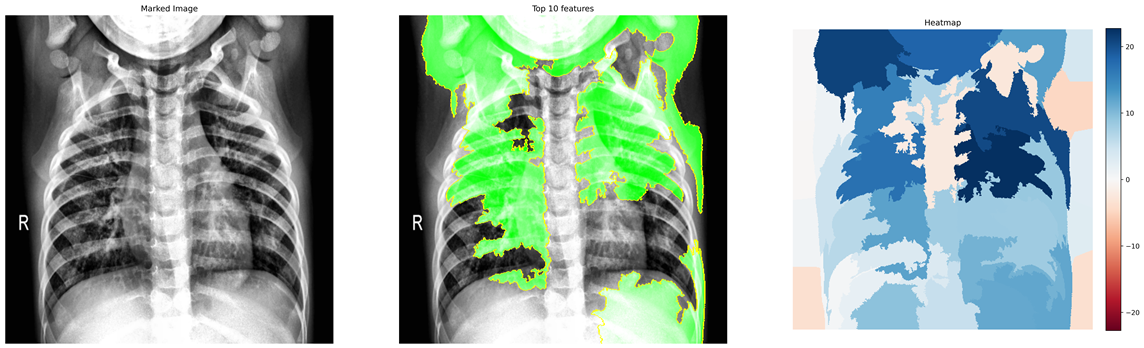

In this work, we only consider the CXR images in a frontal view, namely Poster anterior (PA) and Erect anteroposterior (AP). The first two databases in the above list comprise 520 such images. For the training purpose, we have used these images along with 520 CXR images of normal and pneumonia cases from COVID-19 Radiography Database (Kaggle) COVID19R73:online and Mendeley Chest X-ray Images kermany2018large . Figures 1(a) and 1(b) depicts the manually marked region of interest that distinguishes between COVID-19 and Pneumonia cases in CXR images. The above regions are marked by a radiologist after clinical evaluation of these CXR images.

Figure 8 (a)-(c) shows images relating to COVID-19, Pneumonia, normal cases, respectively. Each subfigure in a row comprises three images of the same patient relating to a medical condition. In each row, the clinical condition has been marked by a radiologist in the first image. In the second image in the same row, the top 10 superpixels obtained using LIME have been marked using green and red colors. Superpixels contributing toward and against the predicted class appear in green and red colors, respectively. Finally, the third image in the same row depicts the LIME-generated heatmap corresponding to the second image. The intensity of the blue color of a particular region in the heatmap corresponds to its relative significance in predicting its class. A radiologist confirmed that in the case of Anteroposterior (AP) chest radiograph (Figure 8(a)), the ill-defined area of ground glass haze in the right lung parenchyma at mid-zone likely represents COVID-19. Similarly, in the Anteroposterior (AP) chest radiograph (Figure 8(b)), the wedge-shaped area of consolidation in the right lung parenchyma at the upper zone likely represents pneumonia. The radiologist confirmed that the regions (though not all) highlighted by LIME correspond to the affected regions in case of both COVID-19 and Pneumonia. This points to the applicability of COV-ELM in the identification of medical conditions such as pneumonia and COVID-19.